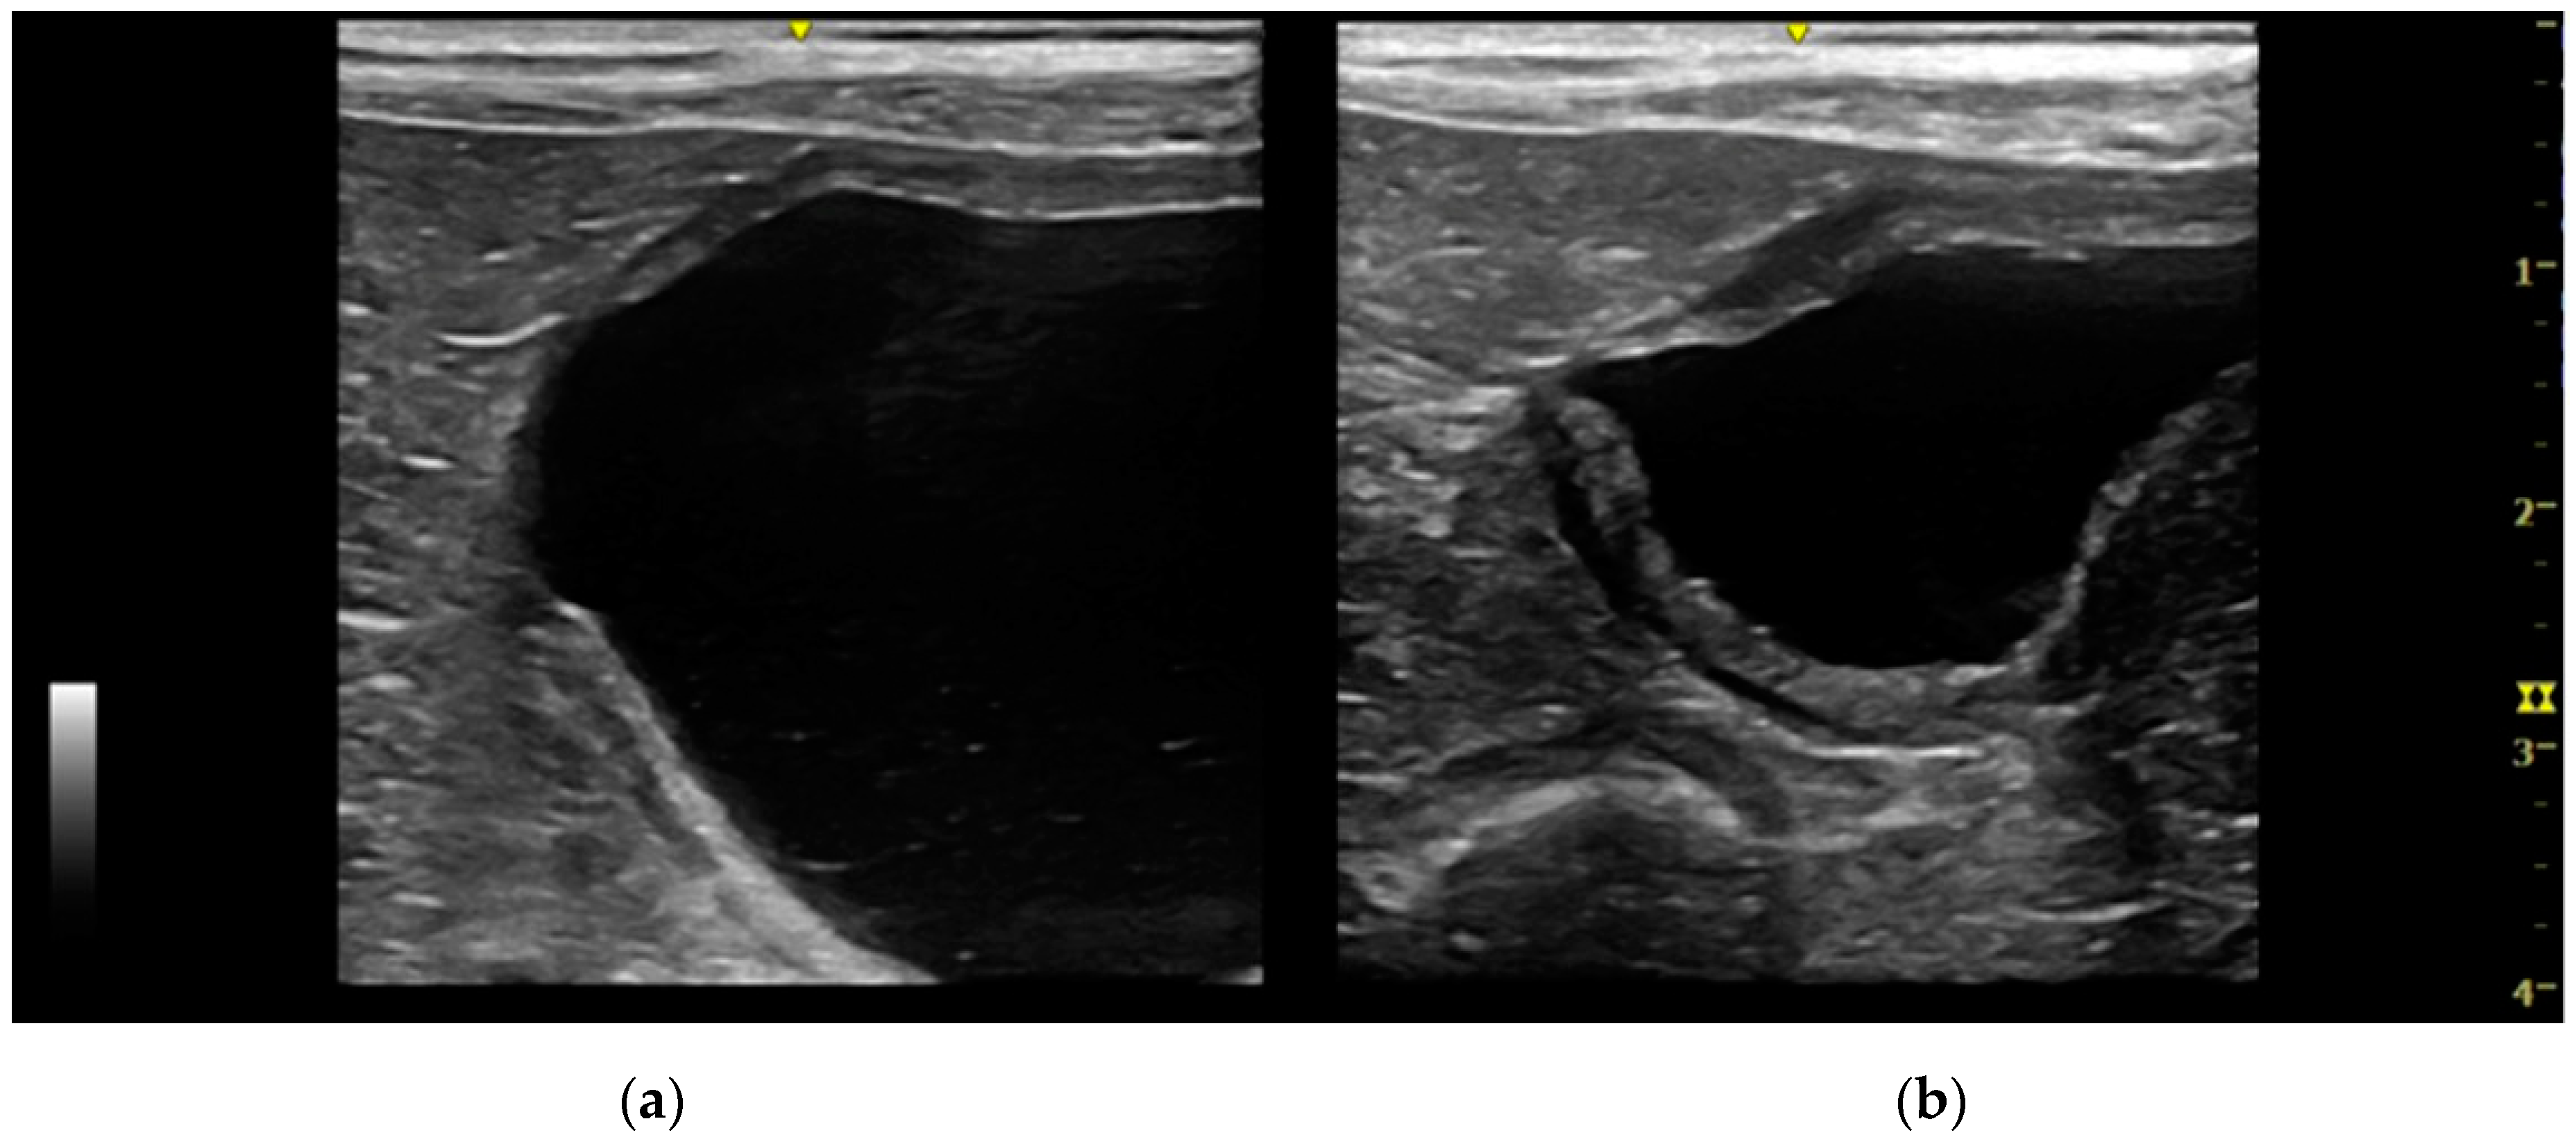

Extramural vesicourachal diverticulum was diagnosed in 20.0% of cats and 18.4% of dogs. Four out of 19 were of large dimensions and extended 1 to 2 cm cranially to the serosa of the urinary bladder apex; 3/19 appeared 0.5–1 cm in diameter, while 12/19 were smaller than 0.5 cm. The wall appeared as a thin hyperechoic line and the content was similar to that of the bladder (Figure 3).

Figure 3. Longitudinal ultrasound image of the urinary bladder in a cat, showing the presence of a small (<1 cm diameter), well-defined, fluid-filled, anechoic structure, protruding beyond the serosal surface of the cranioventral bladder wall, consistent with extramural vesicourachal diverticulum. The bladder presents a moderate, diffuse, thickening of the wall, with an irregular mucosal surface. A moderate amount of echogenic sediment is present in the lumen. Shadowing hyperechoic material adhered to the ventral bladder wall mucosa is also observed, which may represent congealed mineralized sediment.

Figure 7. Two longitudinal ultrasound images of the urinary bladder of a dog with an intramural vesicourachal diverticulum. The images show two different volumes of urine into the bladder lumen. (a) Overly distended: the diverticulum appears as a not very visible focal depression in the cranial-ventral aspect of the bladder, with thinning of the correspondent bladder wall; (b) ddequately distended: the diverticulum appears as an evident, focal, evagination in the cranio-ventral aspect of the bladder.